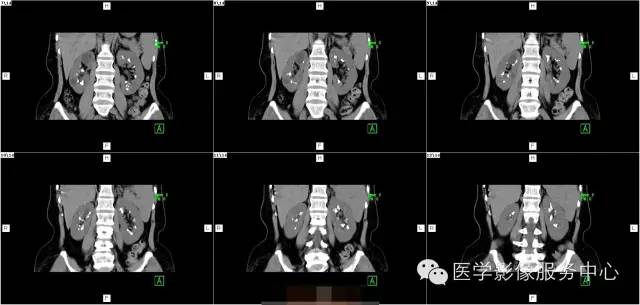

病史:

女,37岁,血尿一周

髓质海绵肾(简称MSK)又称Cacchi Ricci disease,是一种先天发育性肾髓质囊性病变,发生率约1:2000-5000,多见于40-60岁男年,70%为双侧肾脏发病,病变局限于髓质范围内,常累及两侧肾的多数锥体和乳头,形成许多数毫米的囊腔使髓质如海绵状,故名海绵肾,病理特点为集合管远端扩张,形成圆形或不规则型囊腔,囊内壁衬以立方或扁平上皮,囊内充溢脱离的上皮及钙化形成的小结石。

3、CT平扫表现一个或多个肾锥体内散在或蔟团状多发结石,呈花瓣样或扇形分布;部分腹部平片阴性,CT平扫可发现肾锥体内细小的结石。增强扫描表现扩张的肾集合管内有条纹状、刷状、小囊状或扇形的造影剂浓聚。部分患者肾实质内可见多发小囊肿。

1、肾钙盐沉积 :为肾集合管内及其周围弥漫性钙盐沉积,病变广泛,但不伴有集合管扩张,常见于肾小管酸中毒、甲旁亢、特发性高尿酸钙等

2、肾结核 病变不局限于肾乳头部,累及范围广,病灶不规则, IVP检查可显示肾盏虫噬样改变。

3、肾盏内散在小结石与不典型髓质海绵肾鉴别 海绵肾小结石位于肾乳头内,很少大于5mm,位置固定 ,IVP检查可见集合管囊状扩张,B超、CT检查可进一步明确诊断。

4、肾乳头坏死形成的钙化 病变位于肾盏顶部或锥体的尖端,钙化呈环状或三角形,密度均匀,病变中心因乳头坏死呈空腔改变,可伴肾盏变形和肾功能损害。